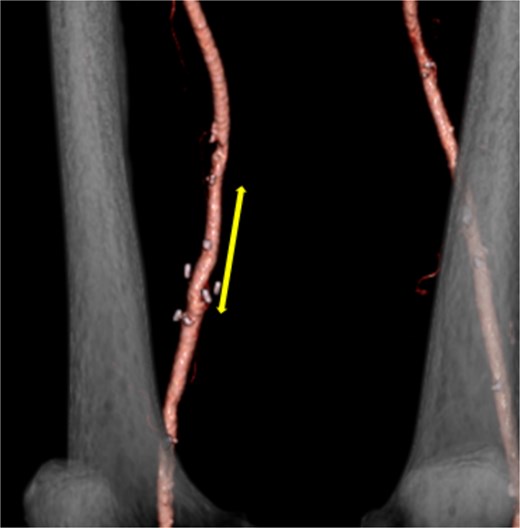

A 62-year-old male patient presented with an asymptomatic 15-mm-diameter right SFA aneurysm on computed tomography (CT). The patient had a history of chronic limb ischemia of the left upper extremity due to proteinase 3-specific antineutrophil cytoplasmic antibody (PR3-ANCA)-associated vasculitis. He also had a history of deep vein thrombosis (DVT) and pulmonary embolism secondary to antiphospholipid syndrome (APS) and systemic lupus erythematous, requiring pulmonary thromboembolectomy, right deep vein thrombectomy, and inferior vena cava filter placement. Although the 12-mm-diameter SFA aneurysm was detected at the time of DVT evaluation, no further imaging follow-up was performed after DVT treatment. Given the aforementioned medical history, the patient was on anticoagulation therapy with 10 mg/day of rivaroxaban and immunosuppressive therapy with 6 mg/day of methylprednisolone and 100 mg/day of azathioprine. A contrast-enhanced CT revealed the right SFA aneurysm, measuring 15 mm in diameter. The aneurysm was located ~6 cm proximal to the knee joint. A comparison with the CT scan for DVT recurrence evaluation obtained 2 years prior revealed an increase in the intraluminal thrombus within the aneurysm (Fig. 1). CT angiography of the distal lower extremity revealed no evidence of occlusion and recurrent DVT.

(a) Contrast-enhanced computed tomography (CT) performed 2 years earlier showed no thrombus in the right superficial femoral artery (SFA) aneurysm. (b) Despite ongoing oral anticoagulation therapy, preoperative contrast-enhanced CT revealed thrombus progression within the aneurysm, which was located 6 cm proximal to the knee and measured 15 mm in diameter. (c) The sagittal section of the contrast-enhanced CT showed an irregular thrombus on the inner wall of the aneurysm (arrow). (d) A three-dimensional-reconstructed contrast-enhanced CT identified the SFA aneurysm (arrow).

Despite the implementation of anticoagulation therapy, the intraluminal thrombus within the aneurysm continued to grow. Consequently, surgical resection was deemed necessary to prevent potential embolization.